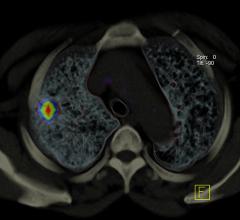

Blue Earth Diagnostics recently announced the results of a pre-planned interim analysis from an investigational clinical trial evaluating the impact of fluciclovine (18F) PET/CT imaging on clinical management of men with biochemically recurrent prostate cancer eligible for salvage therapy.